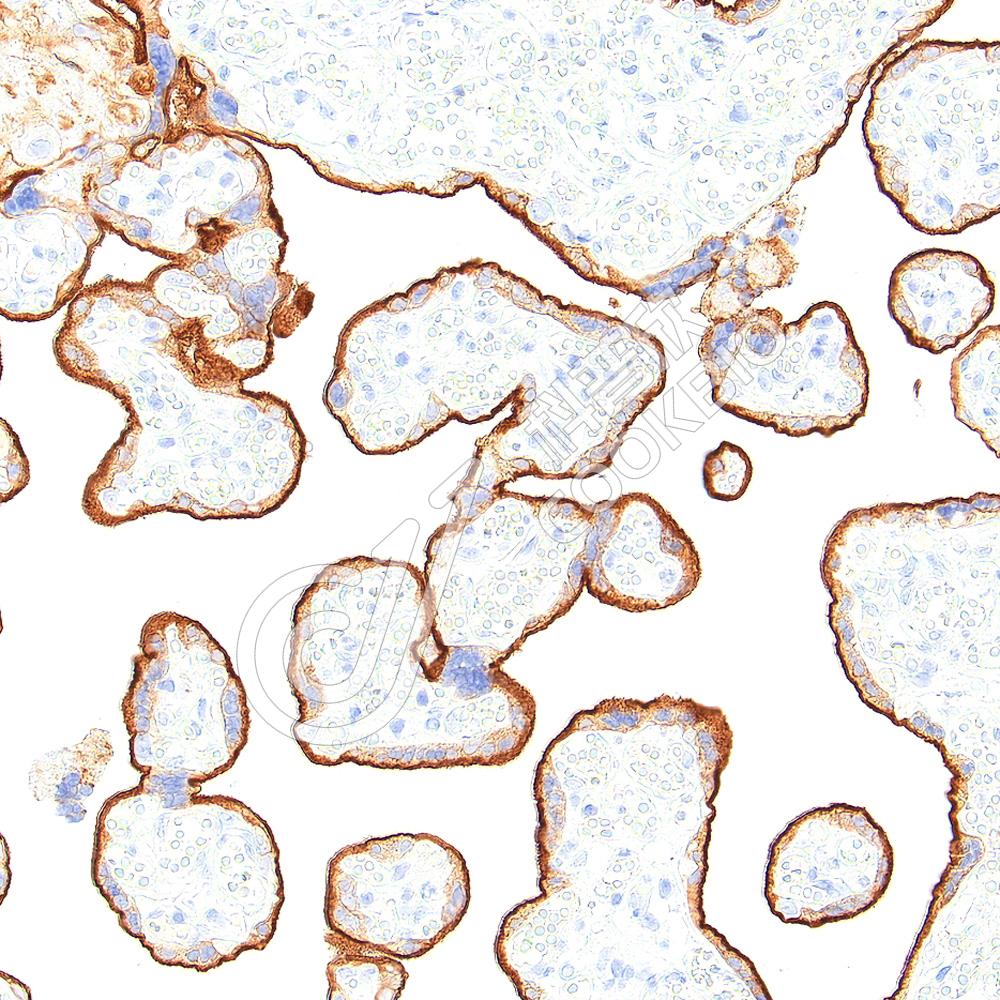

IHC检测PD-L1蛋白(货号 K5467208).

样品: 人胎盘, 4%多聚甲醛 (货号KSG1101) 固定12-24小时.

抗原修复: Tris-EDTA抗原修复液(pH 9.0) (KSG1203), 98℃, 20分钟.

—抗: 1: 300稀释, 4℃ 孵育过夜.

二抗: S-vision免疫组化多聚二抗(山羊抗兔),即用型 (货号KB3906), 室温孵育20分钟.